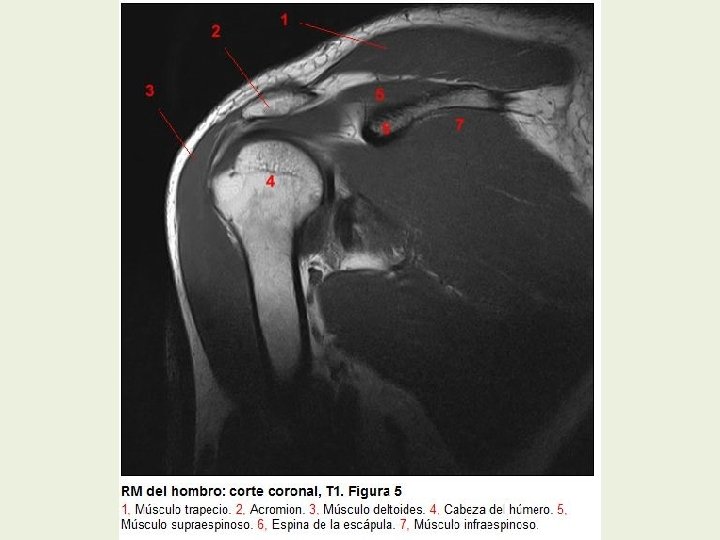

Hombro Cortes coronales RMN